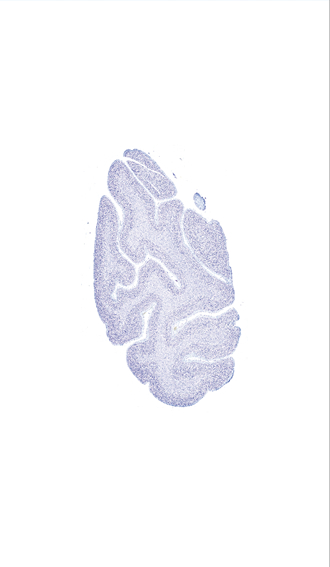

Hi-Resolution Sections · Cells (Nissl Staining) · Virtual Microscopy

Frontal sections (Nissl) from the Atlas Brain:

Slice ID:

r5-0675

Plate NR:

67-68

Position:

94,4 mm